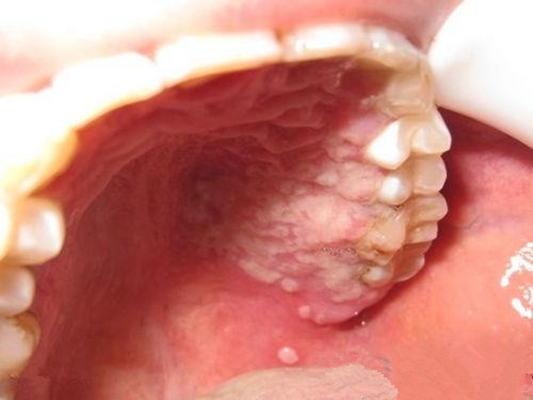

口腔粘膜白斑图片62

口腔白斑

口腔白斑病

这是口腔白斑吗